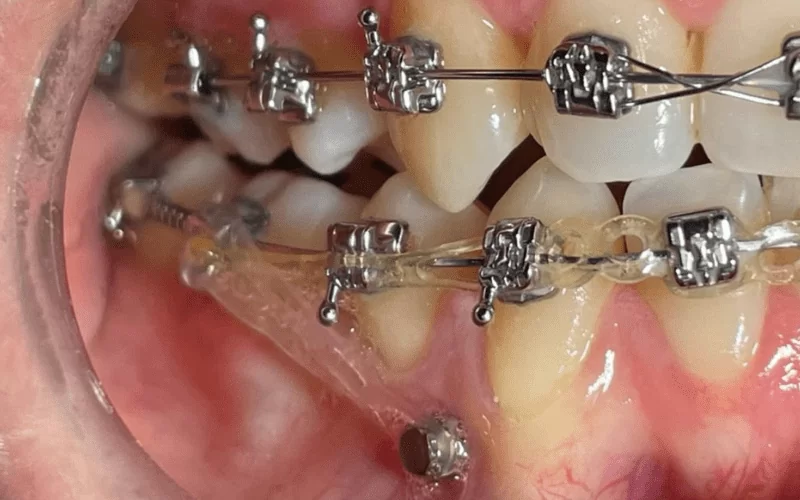

Микроимплантами называют небольшие титановые винты, которые применяются в ортодонтии в качестве вспомогательных элементов. Во время лечения стоматолог-хирург устанавливает их непосредственно в челюстную кость для обеспечения устойчивой опоры и предотвращения смещения элементов ортодонтического лечения.

Небольшие винты устанавливаются временно во время проведения ортодонтического лечения и обычно изготавливаются из титана или его сплавов. Они отличаются высокой биологической совместимостью, но не проходят процесс остеоинтеграции. Установка микроимплантов проста, они обладают высокой стойкостью к силовым нагрузкам и устанавливаются под местным наркозом.

Современные микроимпланты в ортодонтии устанавливаются хирургом-стоматологом между корнями зубов, причем их головка может быть видна над поверхностью зубов. Применение этой передовой методики в ортодонтии позволяет успешно корректировать следующие патологии:

• Использование в ортодонтии: Микроштифты могут использоваться в ортодонтическом лечении для создания каркаса для крепления металлической дуги. По завершении коррекции прикуса вся система с имплантами удаляется.